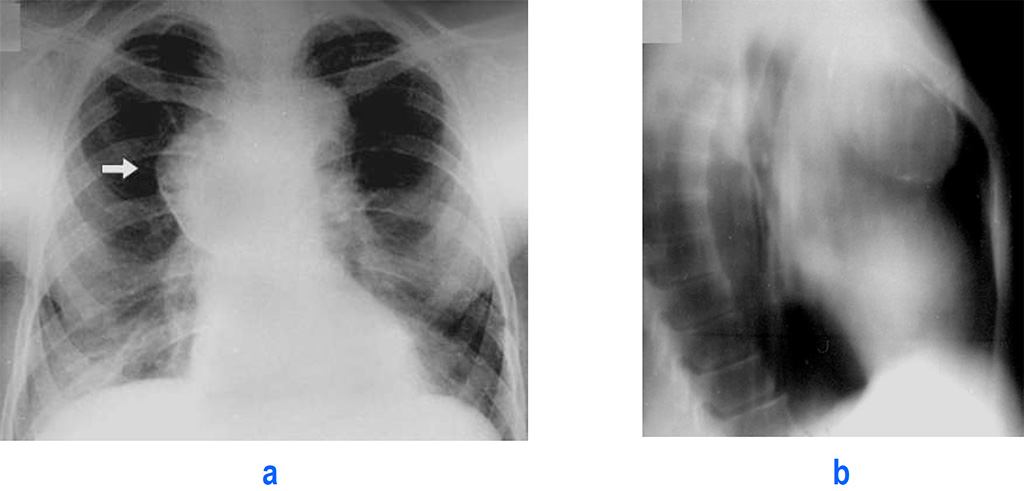

Рентгеновские снимки тератомы средостения: Диагностика и лечение

Раздел: Фотоэссе